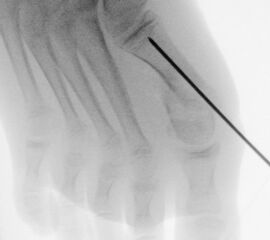

In der minimalinvasiven Fußchirurgie ist es unabdingbar, die Fräse in ihrer Position zum Knochen radiologisch zu kontrollieren, damit vulnerable Wachstumsfugen oder angrenzende Gelenke nicht verletzt werden. Zu diesem Zweck werden mit einem Bildwandler während der Operation die genaue Position der Fräse und der Osteotomieverlauf überprüft, was die Strahlenbelastung im Vergleich zu offenen Verfahren erhöht. Diese Strahlenbelastung hat potenziell einen schädigenden Einfluss auf den noch blutbildenden Knochen von Heranwachsenden. Gesicherte Landmarken am Fuß können die notwendige Zahl der Röntgenbilder und damit die Strahlung minimieren. Ist es erforderlich, mehrere Knochen zu osteotomieren, wie zum Beispiel im Bereich der Kleinzehen, werden anhand der Landmarken kleine Injektionsnadeln auf Höhe der geplanten Osteotomien vorgelegt und radiologisch im Bildwandler (BV) dokumentiert (Abb. 11). Ein solches Bild schafft eine gute Orientierung, sodass auf radiologische Kontrollen intraoperativ weitestgehend verzichtet werden kann.

Abb. 11: Lokalisation mehrerer Stichinzisionen mit einem Röntgenbild.

Zum Lesen der Bildbeschreibung und zur Vollansicht bitte das Bild anklicken. Bild: A. Helmers.